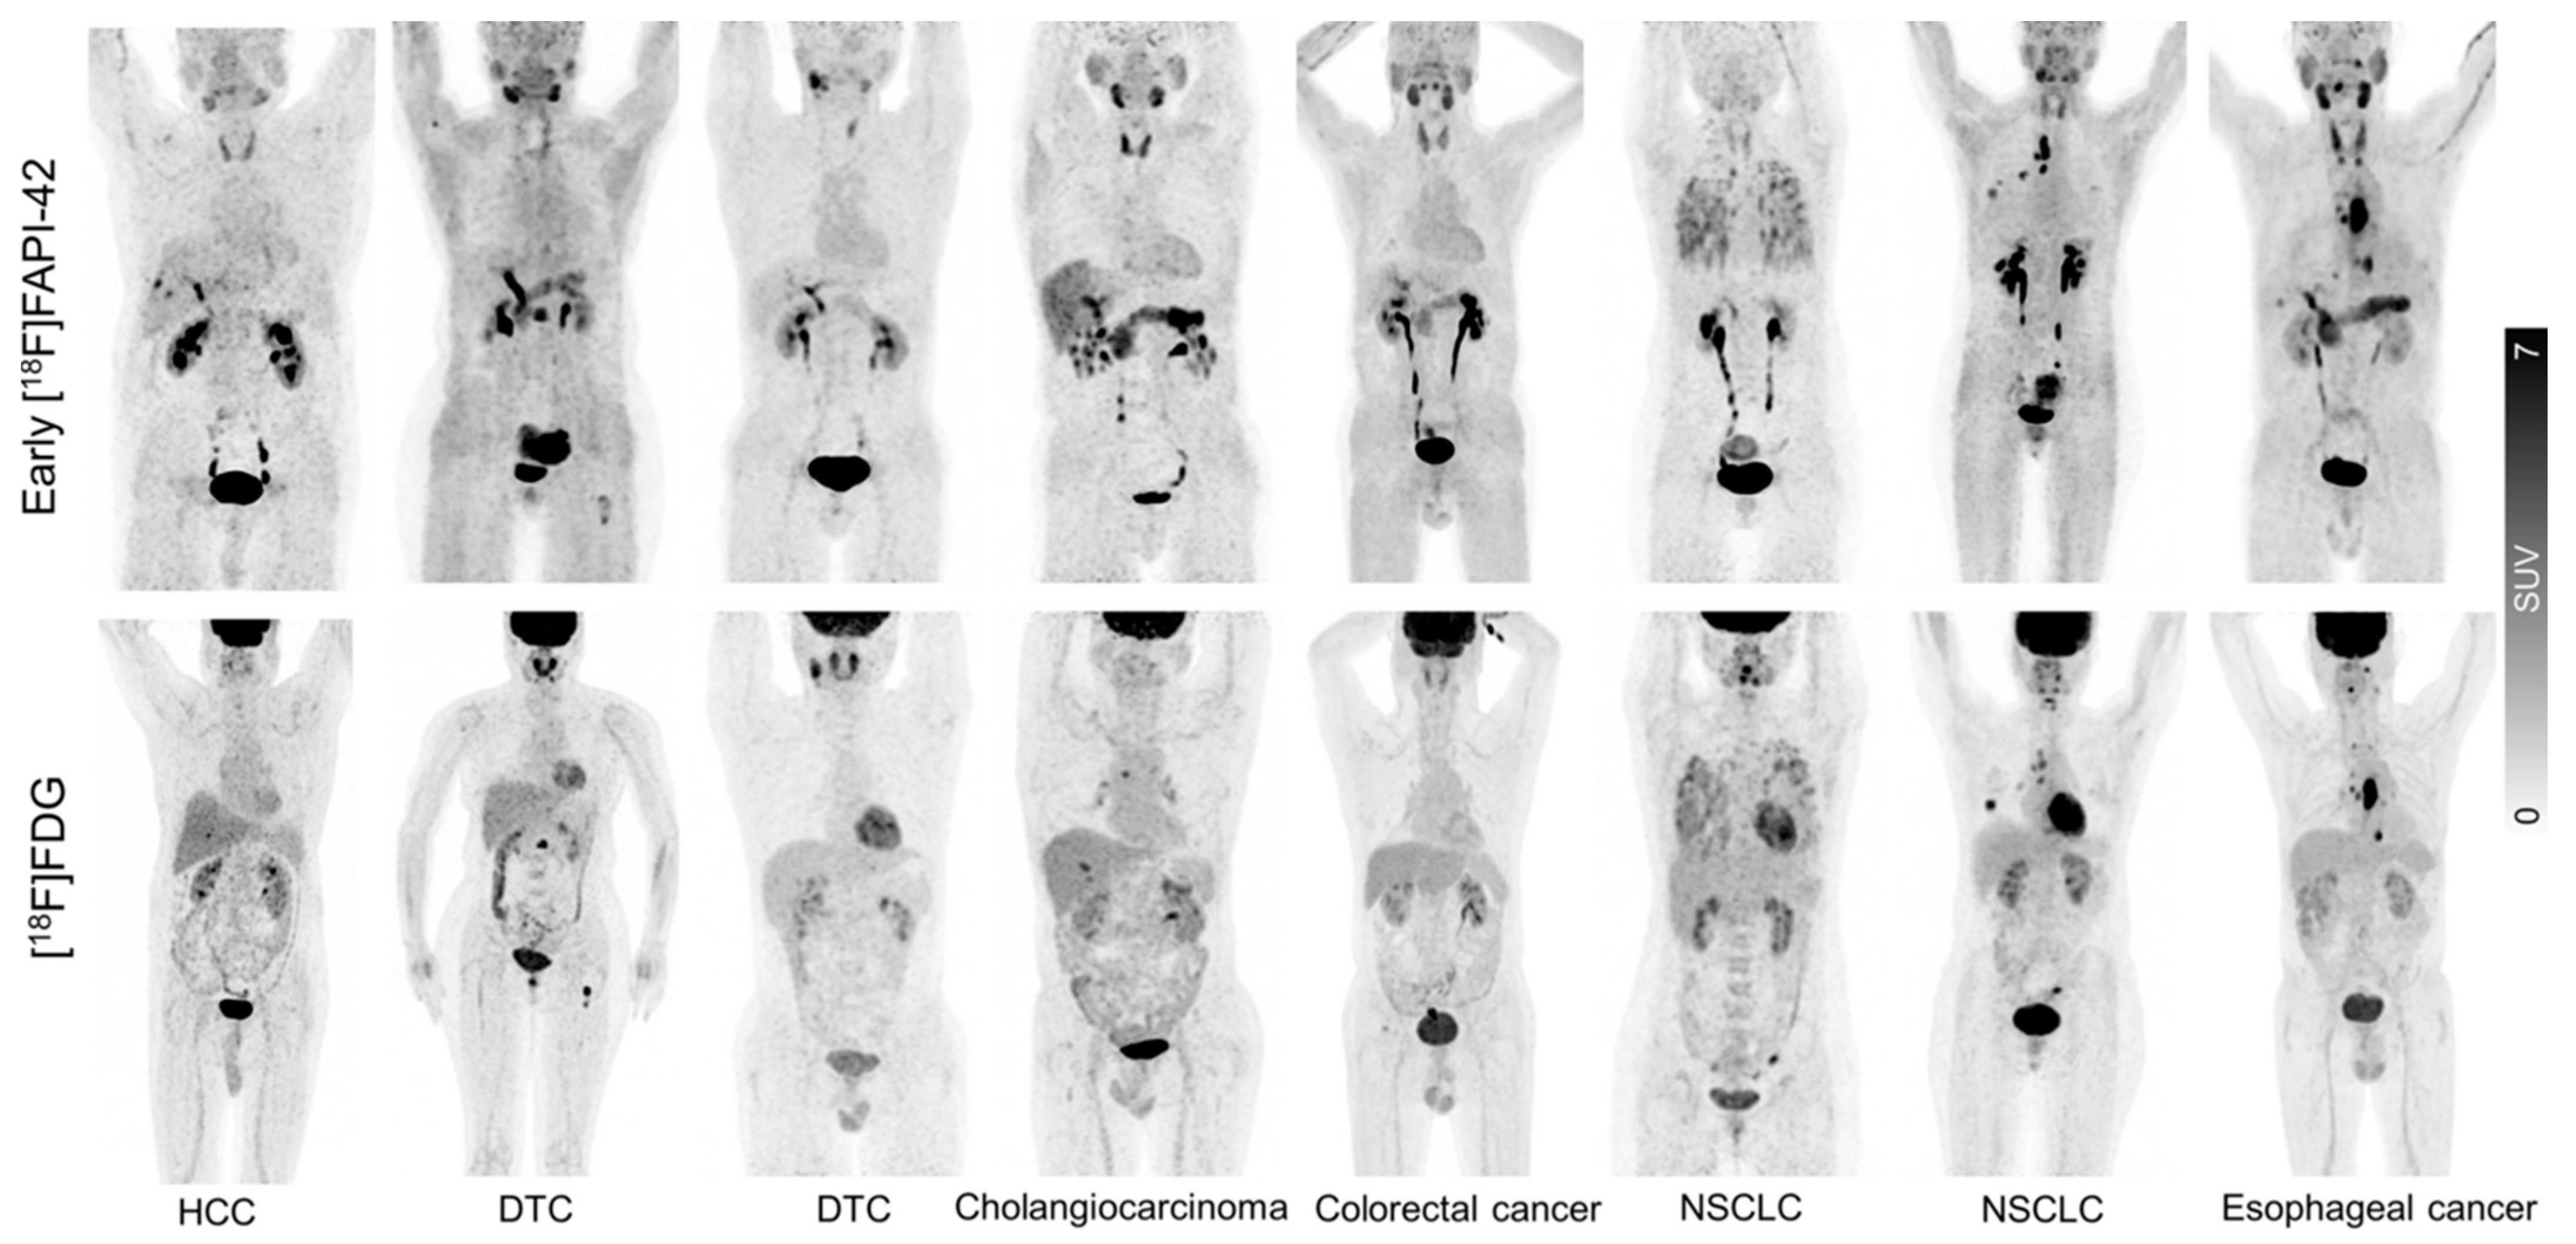

- Hu, K.; Wang, L.; Wu, H.; Huang, S.; Tian, Y.; Wang, Q.; Xiao, C.; Han, Y.; Tang, G. [18F]FAPI-42 PET Imaging in Cancer Patients: Optimal Acquisition Time, Biodistribution, and Comparison with [68Ga]Ga-FAPI-04. Eur. J. Nucl. Med. Mol. Imaging 2022, 49, 2833–2843. [Google Scholar] [CrossRef]

- Mu, X.; Mo, B.; Qin, J.; Li, Z.; Chong, W.; Zeng, Y.; Lu, L.; Zhang, L.; Fu, W. Comparative Analysis of Two Timepoints on [18F]FAPI-42 PET/CT in Various Cancers. Eur. J. Hybrid Imaging 2023, 7, 27. [Google Scholar] [CrossRef]

- Mu, X.; Huang, X.; Jiang, Z.; Li, M.; Jia, L.; Lv, Z.; Fu, W.; Mao, J. [18F]FAPI-42 PET/CT in Differentiated Thyroid Cancer: Diagnostic Performance, Uptake Values, and Comparison with 2-[18F]FDG PET/CT. Eur. J. Nucl. Med. Mol. Imaging 2023, 50, 1205–1215. [Google Scholar] [CrossRef]